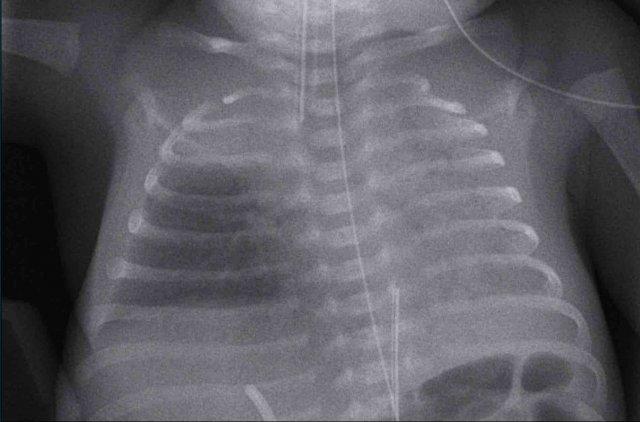

Trẻ sơ sinh đủ tháng, 2 giờ sau sinh mổ chủ động với một số dấu hiệu suy hô hấp.

Image

- Mild

hyperinflation - Subtle

interstitial linings on both sides - Some pleural

fluid on the right side (arrow). - Skin fold on the right

side

Sau

liệu pháp hỗ trợ, tình trạng suy hô hấp đã biến mất vào ngày hôm sau.